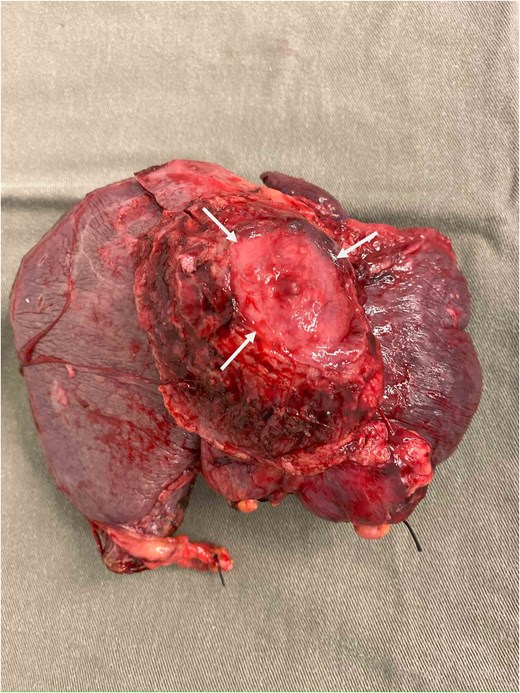

During operation, an exophytic 7 cm segment 4 tumor was found invading superiorly to left hemidiaphragm and pericardium, inferiorly invading to first part of duodenum. A cuff of duodenal wall was removed with tumor and the duodenal defect was closed primarily with 3/0 PDS. Part of the left hemidiaphragm together with pericardium was resected, the heart and left lung were exposed (Fig. 3). The diaphragmatic/pericardial defect was closed with Gore-Tex mesh with single layer continuous 3/0 Prolene (Fig. 4). Air was expelled through an under-water seal catheter placed in the pleural cavity before suture was tightened and tied. Left trisectionectomy was then completed (Fig. 5). The patient developed intra-abdominal collection after surgery which resolved with percutaneous drainage. Pathology confirmed a 7 cm ICC, there was evidence of rupture with abscess formation, and adhesion but no direct invasion to duodenum and diaphragm (Fig. 6). The resection margin was clear. No satellite lesion or microvascular invasion. CEA decreased to normal level after surgery. The patient declined adjuvant chemotherapy.

Specimen showing removed liver with attached pericardium (arrows).